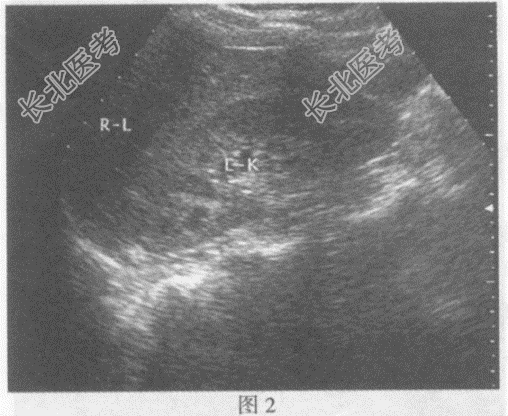

- 单项选择题临床资料:女, 34岁,右位心。

超声综合描述: 右上腹可见脾脏(图1),左上腹可见肝脏(图2), 腹主动脉位于脊柱右前方,下腔静脉位于脊柱左前方(彩图), 胆囊位于左上腹(图3),各脏器形态大小回声未见异常。